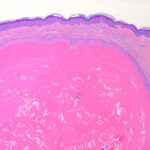

The epithelial cells close to the cystic cavity appear swollen and are filled with pale cytoplasm . These swollen cells do not produce a granular layer but generally undergo abrupt keratinization, although nuclear remnants are occasionally retained in a few cells. The content of the cysts consists of homogeneous eosinophilic material . |

Whereas focal calcification of the cyst content does not occur in epidermal cysts, foci of calcification are seen in approximately one fourth of trichilemmal cysts . A considerable foreign-body reaction results when the wall of a trichilemmal cyst ruptures, and the cyst may then undergo partial or complete disintegration. |